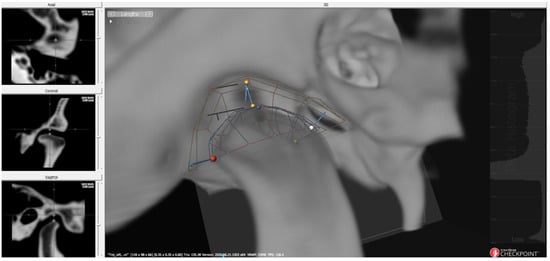

2.3.1. 3D Condyle–Fossa Relationship Analysis

2.3.2. Post-Superimposition Analysis of the Mandible